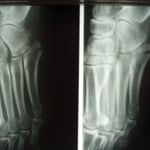

○第5中足骨骨折

足首をねんざした時に同時に起きる骨折です。

昔から「げた骨折」と呼ばれたもので、当時は下駄のひもが切れた時足の外側が地面に叩き付けられたために骨折したからでしょうか・・?今でも「げた」言えばこの骨折意味します。 整骨院でもよく扱う骨折です。

通常整形外科では足の指先から膝下までのギプスをまき足底にヒールと呼ぶゴムパットをつけます。

ただこのギプスは外も家の中も常にブーツを履いた様なもので、しかもヒールが片方だけにあるので

非常に歩きにくいものです。簡単に言えば片足に10センチのヒールのあるブーツ、片方は裸足といった具合です。

また一ヶ月ほど固定するので夏などは想像したくありません。私も整形外科勤務時はこのギプスを患者さんに巻いていましたが、取り外すときは息を止めてギプスカッターを使用していました。(くさ~)

当院ではブーツの様なギプスは巻かず、副子を外からかぶせ包帯で固定します。

毎日固定は外し患部の清拭、浮腫の除去、動かせる関節は早期からリハビリ。これにより患者さんは気持ちよく過ごすことができます。固定期間からリハビリを開始するので関節の拘縮も防ぎ早期回復につながります。